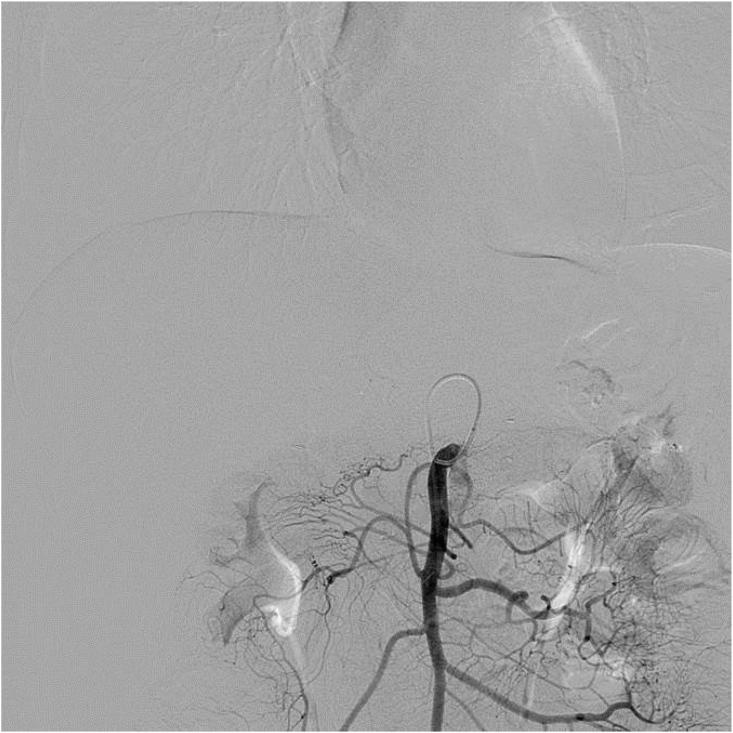

All TAI procedures were considered successful (total 85 times), withan average of 4.25 ± 1.55 procedures per patient. The treatment regimen involved 3 procedures in 10 cases, 4 procedures in 2 cases, 5 procedures in 2 cases, 7 procedures in 1 case and 8 procedures in 1 case. Five of the nine patients who did not undergo surgical resection showed a flaky, pancreatic area that showed lighter staining on superior mesenteric artery angiography (Fig. 1, Fig. 2). The remaining 15 patients showed no significant tumor staining (Fig. 3, Fig. 4).

Fig. 4.

DSA without tumor staining when angiography is performed at the superior mesenteric artery.

The efficacy of chemotherapy drugs depends on the drug concentration in the tumor and the contact time of the drugs within the carcinoma cells. The fibrous capsule surfacing PC challenges the penetration of chemotherapeutics. Additionally, PC often expresses high levels of multidrug resistance, resulting in rapid clearance of chemotherapeutic drugs from the tumor cells. Therefore, systemic chemotherapy does not result in a better prognosis. The principle of TAI is based on a local injection of high concentrations of drugs directly into the tumor tissue through the pancreatic artery or the parent artery segment. It increases the concentration and action time of the drugs in the tumor microenvironment to deliver toxicity to the tumor tissue and to overcome therapy resistance resulting in apoptosis and necrosis of PC cells and improving the therapeutic effect.11,14 This high local concentration of drugs affects only the pancreas with reduced side effects in all other organs.15 Thus, relative to intravenous chemotherapy, direct infusion of drugs intra-arterially leads to secondary perfusion through the portal vein and effectively kills tumor cells in the portal vein system. This either reduces or delays the occurrence of liver metastasis and improves the survival time of patients.16,17 We presume that in surgically resected patients with PC, postoperative intra-arterial infusion chemotherapy can destroy micrometastases that existed before surgery, thereby preventing the development of local recurrences and liver metastasis. In this study, patients treated with TAI had only mild fever (3/20) and nausea and vomiting (2/20) as side effects. Compared with the side effects of systemic chemotherapy and radiotherapy, these are almost negligible. During follow-up, also only four patients developed liver metastases (4/20). In fact, one patient who had undergone surgical resection showed complete remission at > 72 months of follow-up (Figs. 3 and 4).